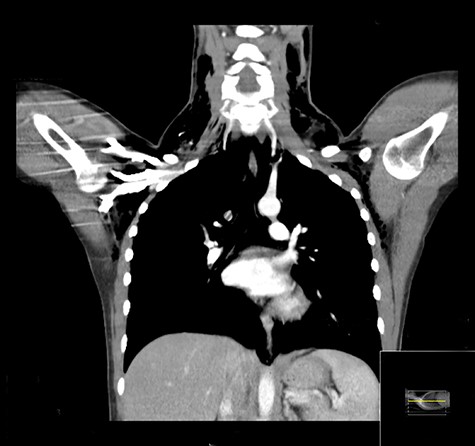

An urgent chest X-ray revealed extensive bilateral subcutaneous emphysema throughout the thorax and base of the neck with no visible pneumothorax or pleural effusion (Fig. 1). Thoracic and cervical computed tomography (CT) with contrast revealed a moderate pneumomediastinum and extensive subcutaneous emphysema throughout the neck, supraclavicular fossae, axillae and upper chest wall with no overt evidence of esophageal injury (Fig. 2).

Coronal CT demonstrating extensive surgical emphysema in the neck, supraclavicular fossae, axillae and upper chest wall with moderate pneumomediastinum.